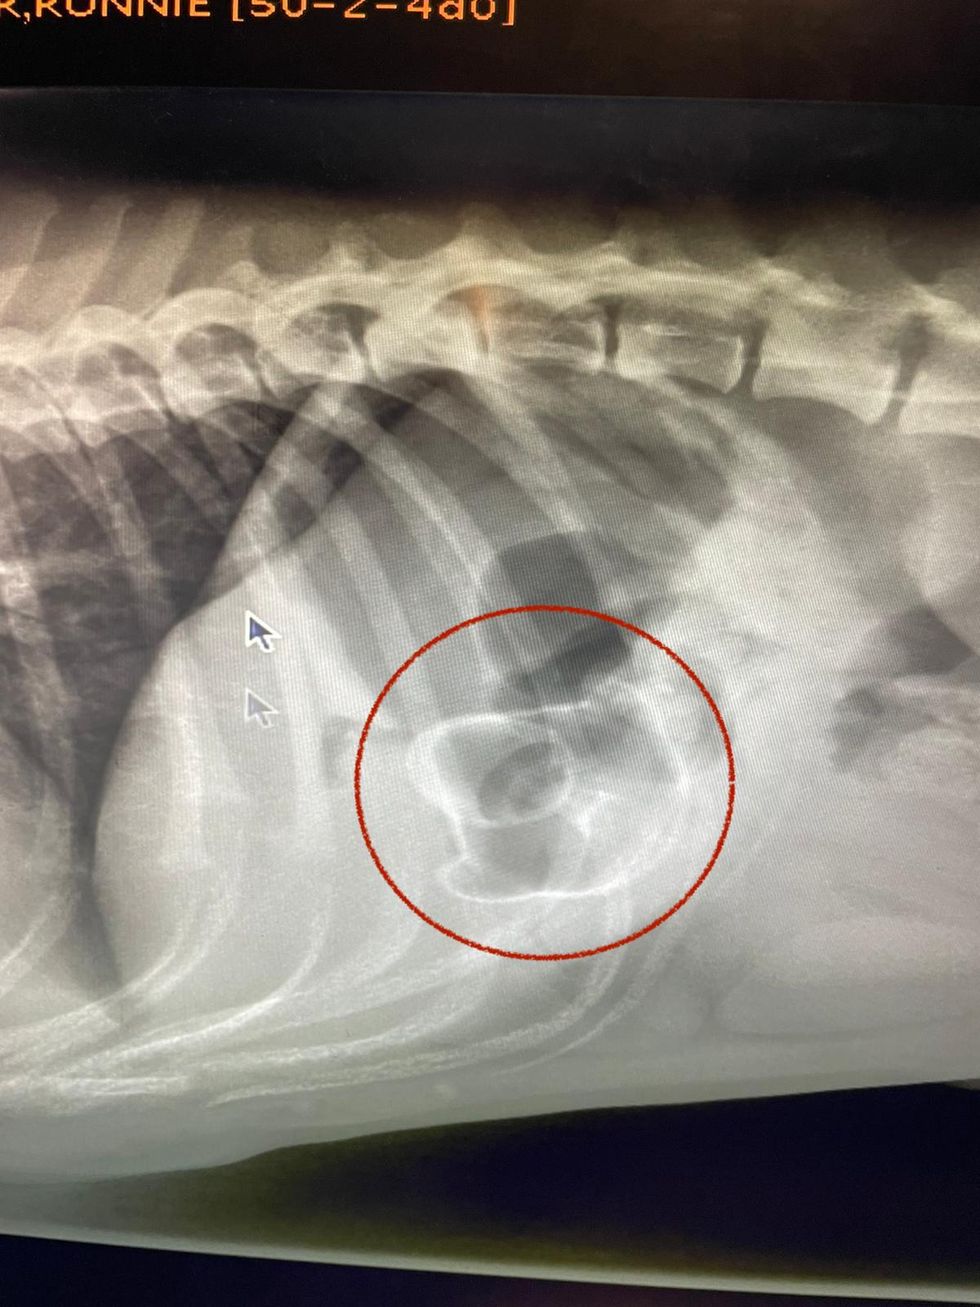

Debs Smith, a senior vet at Pride Veterinary Centre, said: “We sedated Ronnie so we could get an X-ray and it showed the duck really clearly.

“It was still in his stomach and hadn’t passed into the intestines, but we were obviously concerned about it causing an obstruction.